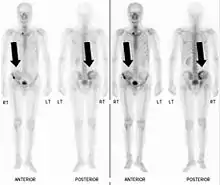

- Vues de fractures pathologiques

Fracture pathologique de l'humérus sur une métastase de carcinome du rein

Fracture pathologique du bras gauche sur une métastase osseuse de cancer du sein

Scintigraphie corps entier avec 99mTc-HDP de la patiente avec une fracture du bras due à une métastase du cancer du sein